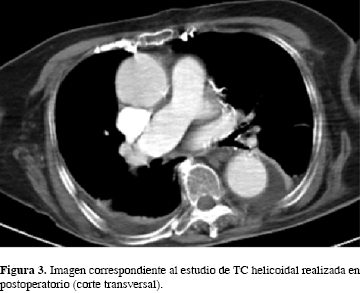

La paciente fue trasladada a la Unidad de Cuidados Intensivos (UCI) con ventilación mecánica, manteniéndose hemodinámicamente estable. No se detectó incremento de enzimas cardíacas (estudio seriado) ni alteraciones analíticas tras la complicación intraoperatoria, por lo que el diagnóstico fue embolismo gaseoso durante el tiempo de lavado femoral con el sistema CarboJet®. La paciente permaneció 24 horas en la UCI, posteriormente se trasladó a la planta de traumatología y fue evaluada de nuevo por el Departamento de Anestesiología. Se realizó TC helicoidal toracoabdominal con contraste, con hallazgos de moderado derrame pleural bilateral, atelectasias basales y múltiples fracturas costales anteriores (como consecuencia de la resucitación cardiopulmonar) (Figura 3). El ecocardiograma mostró la cardiomiopatía hipertensiva inicial, insuficiencia valvular aórtica y tricuspídea, pero con una fracción de eyección normal. La paciente no tuvo ninguna secuela tras el evento, por lo que, aunque presentó alto riesgo, se realizó un segundo tiempo quirúrgico transcurridos ocho días desde la primera cirugía y se le implantó la hemiartroplastía cementada mediante vástago cementado y cúpula bipolar (Figura 4). En este caso no se produjeron complicaciones intraoperatorias y la paciente se recuperó y comenzó a caminar con un andador cuatro días tras la intervención. Finalmente fue dada de alta seis días después.